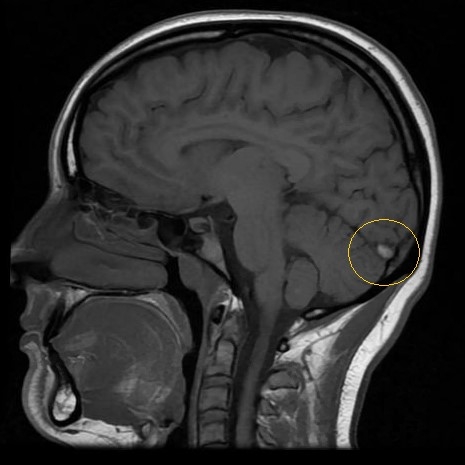

| More Than Just In Your Head: Persistent Headache In A Young Female After Low Impact Head Collision - Page #3 | |||